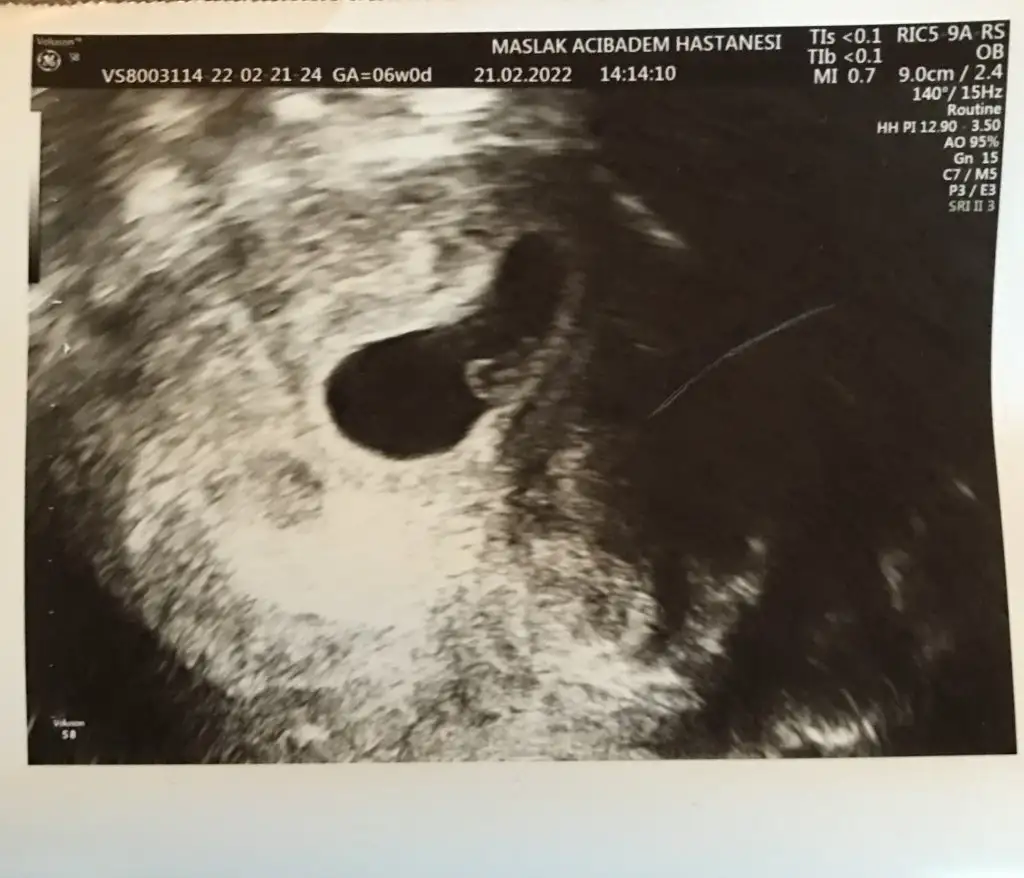

Kızlarrrr bu da benim minnoşum ❤️

Bu arada transfer tarihine göre 6+0 mışım nedense yanlış hesaplamışım 😀

ah canım benim teşekkür ederim. evet gelişimi normal dedi baksana nası şekillenmiş ultrasonda :KK36: